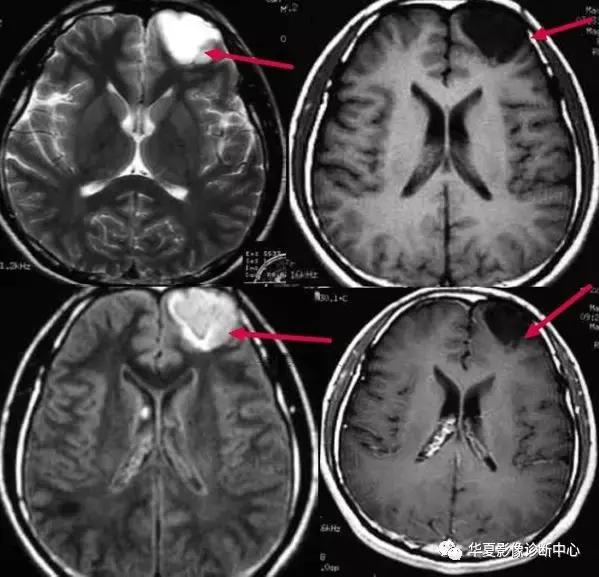

一、常春藤征:

该征是指烟雾病患者MR检查增强扫描时图像上观察到沿柔脑膜分布的点状或线状强化信号影,因类似爬行在石头上的常春藤而命名。文献报道这种征象出现率约70%,并提出其对烟雾病的诊断具有特异性。其形成主要是双侧颈内动脉、大脑前、中动脉狭窄或闭塞后,颈外动脉及椎-基底动脉系统参与代偿性供血的侧支循环血管,包括大脑后动脉、脑膜中动脉、颞浅动脉、枕动脉,沿双侧大脑皮层柔脑膜分布。有研究报道FLAIR图像亦可观察到常春藤征,表现为柔脑膜弥漫性高信号改变。FLAIR序列是水信号为零时的反转脉冲序列,由于FLAIR能够有效地克服脑脊液在T2WI呈高信号所致的部分容积效应和伪影的影响,敏感地反映蛛网膜下腔轻微信号强度的改变,对蛛网膜下腔病变如蛛网膜下腔出血、脑膜炎和脑膜转移瘤等比常规T2WI敏感。在烟雾病患者FLAIR图像上的常春藤征的产生机制仍未完全清楚,目前存在几种不同的说法:1)脑底异常血管网和脑表面代偿性侧支循环血管与柔脑膜血管吻合,形成皮层柔脑膜侧支血管网,由于其血流速度缓慢,而表现为高信号;2)皮层软脑膜侧支吻合血管网的柔脑膜动脉扩张;3)皮层柔脑膜充血、水肿、增厚。有研究者观察到有效的血管重建术后烟雾血管和皮层柔脑膜点状或线状高信号减少甚至消失,患者临床症状明显改善,提示FLAIR图像上柔脑膜点状或线状高信号信号改变为皮层柔脑膜血管充血、水肿和增厚。这种表现是由于颈内动脉及大脑中动脉狭窄、闭塞后,颈外动脉及椎-基底动脉系统参与代偿性供血,通过DSA检查可见扩张的颈外动脉系统及大脑后动脉参与形成的柔脑膜侧支血管网,颈内动脉狭窄或闭塞程度越严重,柔脑膜高信号的范围越广泛,其常春藤征表现越明显。常春藤征的轻重与病情进展情况有关。根据DSA表现,烟雾病的病程分为6个阶段:1)颈内动脉分叉段狭窄,通常为双侧性,仅见颈内动脉末端和(或)大脑前、中动脉起始段狭窄;2)颅底异常血管网形成;3)颅底烟雾状血管更明显,大脑前、中动脉进一步狭窄或闭塞;4)随病程进展,烟雾状血管开始减少,经颈外动脉代偿供血增加;5)第4阶段进一步进展;6)颅内主要动脉完全消失,颅底异常血管网亦消失,此时大脑主要依靠颈外动脉代偿供血。由于常春藤征的形成主要是一侧或双侧颈内动脉、大脑前、中动脉狭窄或闭塞后,颈外动脉及椎-基底动脉系统参与代偿性供血的侧支循环血管,故常春藤征主要在病程后期才出现。常春藤征在各期表现程度不同,部分FLAIR图像未见到常春藤征,可能有二种原因:1)由于其颈内动脉闭塞后侧支循环形成不足,代偿能力差,此时可见脑实质内改变明显,本研究中表现为大面积脑梗死、脑出血的患者FLAIR图像上均未见常春藤征;2)病情较轻,未形成完整的侧支循环血管。常春藤征首先于烟雾病患者MR增强扫描图像上观察到。有人指出T1增强扫描在诊断烟雾病中比FLAIR图像更有优势,比较增强扫描所获得图像与同一病例的FLAIR图像,当FLAIR图像上柔脑膜高信号分布范围较小而散在分布时,在T1W增强扫描图像上可以见到明显常春藤征象,但在后者上较难鉴别正常强化的脑膜血管或烟雾病侧支循环血管。另外,FLAIR图像能清晰显示脑内缺血灶、梗死灶、脑软化灶等继发性脑实质改变。 在烟雾病患者,常春藤征需与脑膜炎及蛛网膜下腔出血鉴别。脑膜炎在病理上主要是脑膜增厚及肉芽组织增生,其诊断主要根据临床表现及脑脊液检查,部分患者MR FLAIR图像上可见脑膜高信号表现,可错认为常春藤征,但脑膜炎病变主要分布脑颅底及双侧颞叶,鞍上池脑膜明显,有时可见邻近脑实质受累呈高信号。蛛网膜下腔出血患者MR FLAIR图像上亦可见到线状高信号改变,但其主要分布在蛛网膜下腔,沿脑沟分布,柔脑膜未见高信号,容易与常春藤征混淆,结合T1WI有助于鉴别诊断。烟雾病患者MR FLAIR图像常春藤征,主要分布在额顶叶。鞍上池脑膜明显,有时可见邻近脑实质受累呈高信号